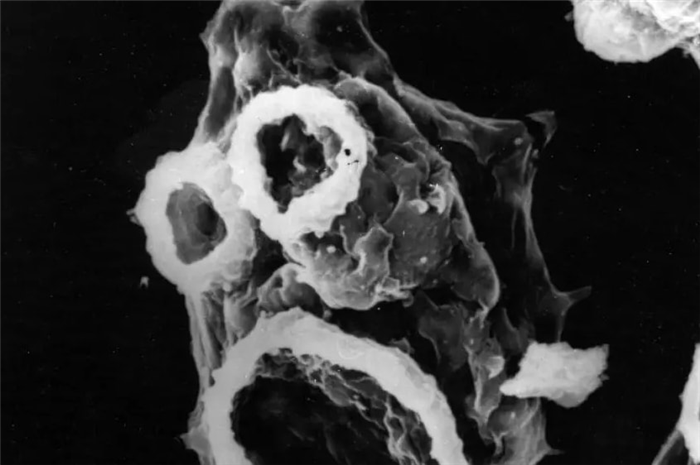

При вскрытии наблюдается выраженный отек головного мозга , гиперемия мозговых оболочек с возможным наличием гнойного экссудата в бороздах у основания мозга и мозжечка ; повреждение спинного мозга непостоянно. Из кист амебы присутствуют в большем или меньшем количестве в спинномозговой жидкости и субарахноидальном экссудате (см. Мозговые оболочки ). Он обнаруживается в периваскулярном кластере в пространствах Вирхова-Робена или в сером веществе, но очень редко в белом веществе (см. Нейроанатомия ).